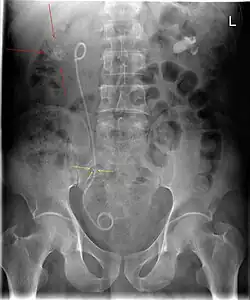

Der retrograde Eingriff kann entweder in Lokalanästhesie oder in Vollnarkose durchgeführt werden. Der Patient wird in der Steinschnittlage gelagert. Mit einem Zystoskop (Blasenspiegel[22]) oder einem Ureterorenoskop wird über die Harnröhre vorgehend die Blase dargestellt. Von dort wird über einen Arbeitskanal unter Sicht ein perforierter Ureterkatheter in den Harnleiter vorgeschoben. In der Regel werden dabei die ableitenden Harnwege per lokaler retrograder Kontrastmittelgabe und Durchleuchtung dargestellt. Das im Nierenbecken liegende Ende des Katheters rollt sich in Form eines „J“ ein, genauso das in der Harnblase liegende Ende, daher der Name „Doppel-J-Schiene“. Beide „J“ führen zu einer sicheren Lage des Katheters.[14]

Die passende Schienenlänge wird anhand der Körpergröße des Patienten oder mithilfe eines Röntgenbildes ermittelt. Sie beträgt beim Erwachsenen meist zwischen 24 und 30 Zentimetern. Der Außendurchmesser beträgt zwischen vier und zehn Charrière (1,3 bis 3,3 mm).[14] Die Innendurchmesser (Kaliber) unterliegen materialabhängig großen Schwankungen.